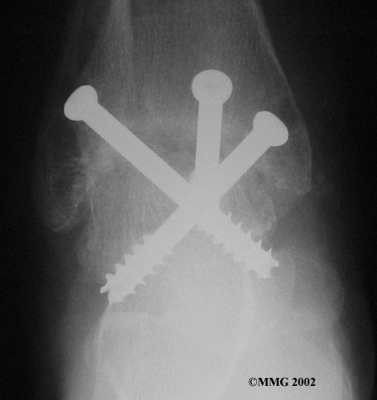

Ankle Fusion

When the ankle joint becomes so painful that it is difficult to walk, surgery may be suggested to fuse the ankle joint. An ankle fusion is sometimes also called an ankle arthrodesis. In this operation, the three bones that make up the ankle joint (the talus, the tibia, and the fibula) are allowed to grow together, or fuse, into one bone. Once this is done the ankle no longer is able to move, but with a successful fusion the pain is gone. Most people with a successful fusion of the ankle are able to walk without much trouble, and in some cases it is almost impossible to tell that the ankle is stiff. But it is very difficult to run because you lose the ability to push off with the toes. The foot can't bend down.

Most people will need some changes made to their shoes following an ankle fusion. Because the ankle no longer moves, it is difficult to roll over the top of the foot when you take a step. For this reason, shoes are usually fitted with a rocker sole. This allows the shoe to roll instead of the foot. A special heel is sometimes built on the shoe to absorb some of the shock.

The ankle fusion is a good operation, especially for a young, active person. It is usually the preferred option for post-traumatic arthritis of the ankle. Once the ankle is successfully fused it can last a lifetime, and no other operations are expected later unless there are problems. But there are complications associated with the ankle fusion, and not all ankle fusions are successful.

Related Document: FYZICAL Geneva's Guide to Ankle Fusion